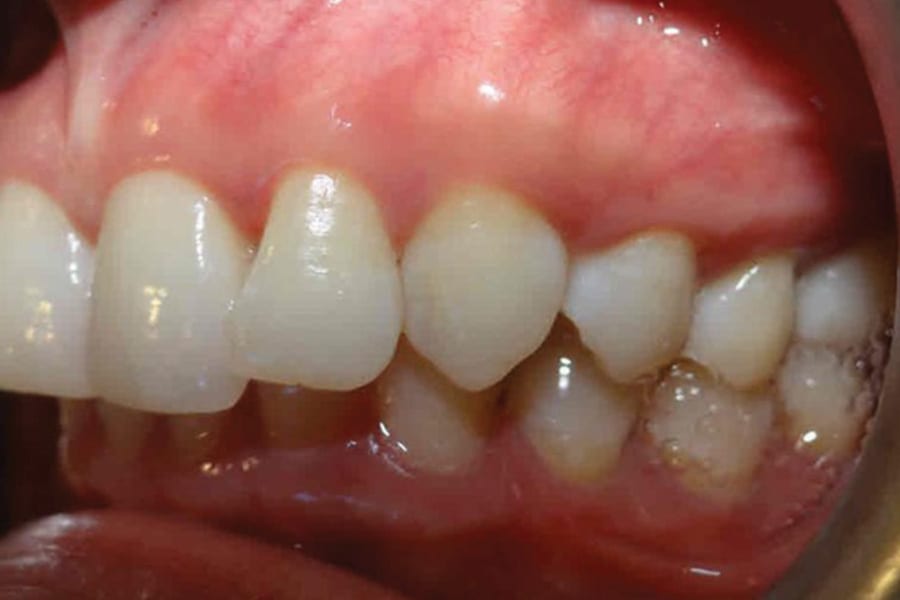

A 35-year-old woman presented with concerns of crowding, bruxism, and bite misalignment, which were associated with a class II malocclusion that would require a combination treatment of expansion, distalization, and molar derotation. ClearCorrect® aligner therapy (Straumann, clearcorrect.com) was selected as the primary modality, as the patient requested a non-invasive, esthetic treatment. The treatment plan was designed to be completed within 6 months of active aligner therapy. Class II elastics were prescribed, and the ClearCorrect FLEX case plan was chosen to allow for refinements, as needed. After comprehensive digital records were taken, the first set of aligners was delivered, engagers were bonded, and the patient was instructed to wear aligners on a 14-day cycle with full-time class II elastic wear. To enhance efficiency, more engagers were placed, including posterior attachments, to maximize control over molar distalization and anchorage. Interproximal reduction of 0.3 mm was performed in a few contacts at the initial appointment to facilitate space closure and alignment. Due to the complexity of the correction and the patient’s history of bruxism, a lower 3-3 bonded retainer was placed, and retainers were fabricated for both arches. The patient expressed a high level of satisfaction with the ClearCorrect aligner therapy, noting the comfort and esthetics of the aligners and the ability to achieve a fully corrected class II occlusion in just 6 months of treatment.